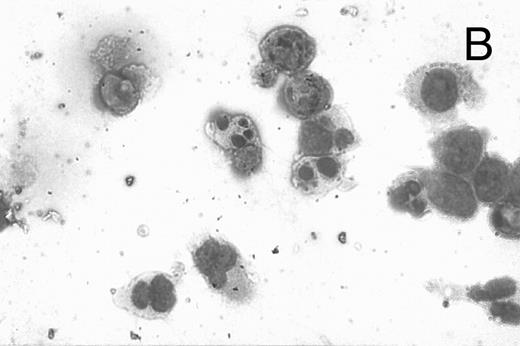

CD437 inhibition of HL-60R growth and induction of apoptosis.Although HL-60R cells are resistant to RA-mediated inhibition of growth,16,17 they are exquisitely sensitive to CD437-mediated inhibition of growth (Fig 1A) with as little as 25 nmol/L CD437 inhibiting growth by approximately 50% (Fig 1B). Similar inhibition of growth was noted in the parental HL-60 cell line (Fig 1C), as well as the RA-resistant K562 leukemia cell line28 (Fig 1D). As evidenced in Fig 1A, there was not only a total inhibition of cellular proliferation in the presence of CD437 but an actual cell loss. We therefore examined whether CD437 induced programmed cell death (apoptosis) in the HL-60R cells. That CD437 indeed induced apoptosis in the HL-60R cells was documented using three independent parameters. (A) HL-60R cells after exposure to 1 μmol/L CD437 displayed marked nuclear fragmentation and chromatin condensation, with the nuclear and cytoplasmic membranes remaining intact (Fig 2), a morphology indicative of apoptosis.29 (B) Incubation of HL-60R cells with 1 μmol/L CD437 resulted in internucleosomal cleavage and laddering of the DNA on gel electrophoresis (Fig 3), a hallmark of apoptosis.29 (C) A number of studies have suggested a critical role for cysteine proteases in the apoptotic process.30-37 Numerous substrates for this family of proteases have now been identified.37-41 PARP, which plays an important role in both DNA synthesis and repair, is cleaved early in the apoptotic process.37 38

A number of antagonists and promoters of apoptosis have recently been described. The bcl-2 family, which now consists of 7 different proteins encoded by 7 different genes, has now been characterized (Vaux and Strasser37 and the references contained within). Bcl-2 and bcl-XL are expressed in numerous cell types and are potent antagonists of apoptosis. We were unable to detect bcl-XL expression in HL-60R or HL-60 cells as has previously been described,43 but found that bcl-2 is highly expressed in these cells and is also cleaved during CD437-mediated apoptosis (Fig 6). Phosphorylation of bcl-2 has been previously described as a mechanism for bcl-2 inactivation during the apoptotic process.44 Whether cleavage of bcl-2 represents another mechanism by which bcl-2 is inactivated remains to be determined. That this cleavage of PARP, CPP32, and bcl-2 does not simply represent random cleavage of a number of proteins is suggested by our inability to detect cleavage of lamin B (data not shown), which is often found cleaved in a variety of forms of programmed cell death.39 41 CD437 also markedly inhibited growth of the K562 cells (Fig 1C) but contrary to HL-60R cells apoptosis was not noted until 144 hours of exposure to CD437, as indicated by internucleosomal degradation demonstrated by gel electrophoresis (Fig 7). We also examined the ability of CD437 to induce PARP cleavage and apoptosis in primary leukemic blasts obtained from a patient with acute myelogenous leukemia. As shown in Fig 8C, enhanced PARP cleavage was noted within 24 hours after exposure to 1 μmol/L CD437, with the apoptotic morphology noted at 48 hours of exposure (Fig 8A and B).

CD437-mediated apoptosis in primary leukemia cells. Leukemic blasts were isolated as described in the Materials and Methods. Cells were exposed to 1 μmol/L CD437 for various periods of time and PARP cleavage was assessed as previously described. (A) Leukemic cells exposed only to vehicle for 48 hours. (B) Leukemic cells exposed to 1 μmol/L CD437 for 48 hours. (C) CD437-mediated PARP cleavage. Lanes 1 and 3, cells exposed to vehicle only for 24 and 48 hours, respectively. Lanes 2 and 4, cells exposed to 1 μmol/L CD437 for 24 and 48 hours, respectively.